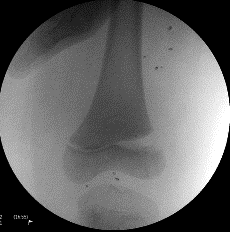

Radiological evaluation

AP and lateral films should be ordered. Oblique views are needed when in doubt or to visualise the fracture better. Stress views may be necessary to identify undisplaced fractures. In infants, separation of the distal femoral physis may be missed. The ossified centre of the epiphysis should always be in the line of the femoral anatomic axis on AP and lateral.

Salter-Harris | Displacement |

---|---|

Type I:Easily missed. Stress views may be necessary. | Hyperextension injury – anterior |

Type II:Most common type. Usually varus or valgus injury. | Hyperflexion injury – posterior |

Type III:Intra-articular. Often best seen on AP X-rays as the physeal component is in the sagittal plane. | Varus injury – medial Valgus injury – lateral |

Type IV:Rare injury but a high incidence of linear physeal bar formation. | |

Type V:Diagnosis usually made retrospectively. |